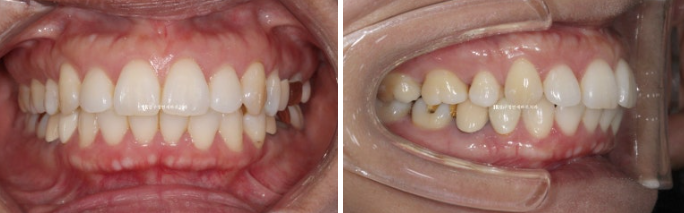

오래 전 교정을 했지만 돌출감과 입이 잘 안다물어져서 입술부전증 치료를 하고자 오신 분입니다.

예전에 교정치료를 받으신 분이라 배열, 교합은 좋습니다.

1년 7개월에 걸친 치료가 마무리가 된 후 전 후 비교입니다.

원래의 배열과 교합은 좋았어서 입안 사진에서는 뻗친 앞니 각도 개선 이외에 별로 달라진 것이 없습니다.